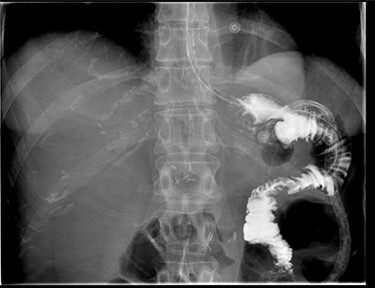

A repeat CT scan was performed, this time with oral contrast, which revealed a large gastrocolonic fistula into the transverse colon (Fig. 1). The patient underwent a gastroscopy and colonoscopy (Fig. 2A–C) which visually confirmed a 50 mm gastrocolonic fistula with a caliber sufficient to allow the passage of a colonoscope with relative ease (~13 mm), and no signs of active Crohn’s disease.

(A) Gastroscopy demonstrating a large gastrocolonic fistula (pink arrow) and gastrojejunostomy leading into the afferent jejunum (yellow arrow). (B) Image of colonoscopy at the splenic flexure demonstrating the gastrocolonic fistula with view of gastric mucosa and nasogastric tube. (C) The gastrocolonic fistula allowed passage of the colonoscope with relative ease. Image of gastric mucosa and nasogastric tube via the gastrocolonic fistula.